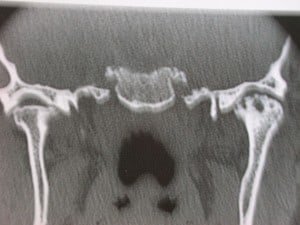

Artrosi dell’Articolazione Temporo-Mandibolare

L’artrosi o osteoartrosi (OA) rappresenta l’artropatia più comune dell’articolazione temporo – mandibolare (ATM).

Come per le altre localizzazioni , anche l’OA dell’ATM (Artrosi dell’Articolazione Temporo-Mandibolare) riconosce una patogenesi multifattoriale, caratterizzata dalla degenerazione progressiva della cartilagine articolare e da alterazioni dell’osso subcondrale.

La sintomatologia è frequentemente caratterizzata da dolorabilità alla palpazione, rumori articolari, in particolare crepitii, riduzione della motilità mandibolare e dolore nell’esecuzione dei normali movimenti.